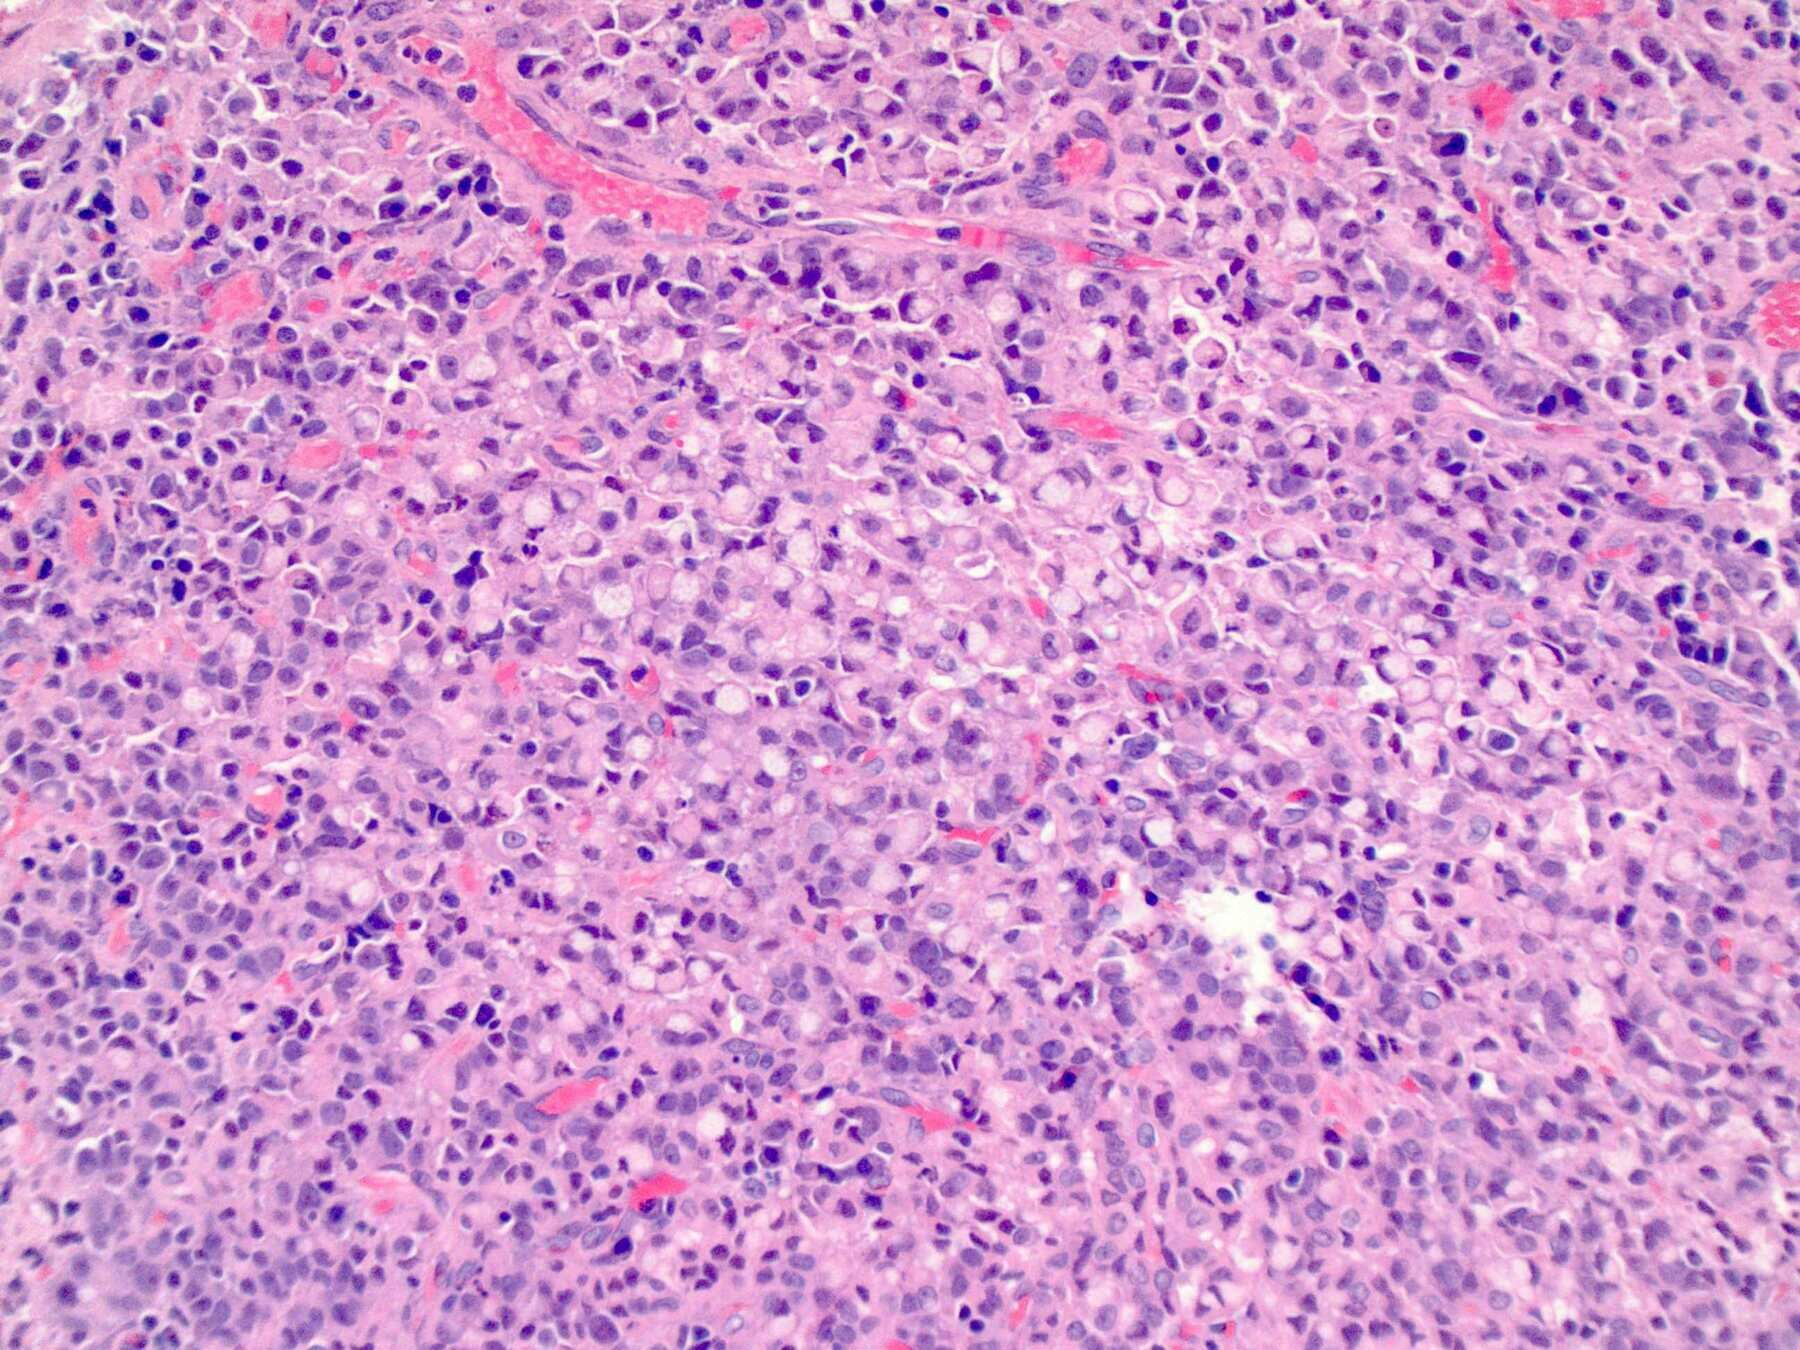

腺癌(Adenocarcinoma)

pictures from Pathology Outlines

Tubular Pattern